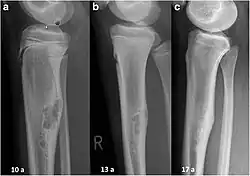

| Non-ossifying fibroma of tibia | |

The most common bone tumor is a non-ossifying fibroma.[4] Average five-year survival in the United States after being diagnosed with bone and joint cancer is 67%.[5] The earliest known bone tumor was an osteosarcoma in a foot bone discovered in South Africa, between 1.6 and 1.8 million years ago.[6]

Primary tumors of bone can be divided into benign tumors and cancers. Common benign bone tumors may be neoplastic, developmental, traumatic, infectious, or inflammatory in etiology. Some benign tumors are not true neoplasms, but rather, represent hamartomas, namely the osteochondroma. The most common locations for many primary tumors, both benign and malignant include the distal femur and proximal tibia (around the knee joint). Examples of benign bone tumors include osteoma, osteoid osteoma, osteochondroma, osteoblastoma, enchondroma, giant cell tumor of bone and aneurysmal bone cyst.